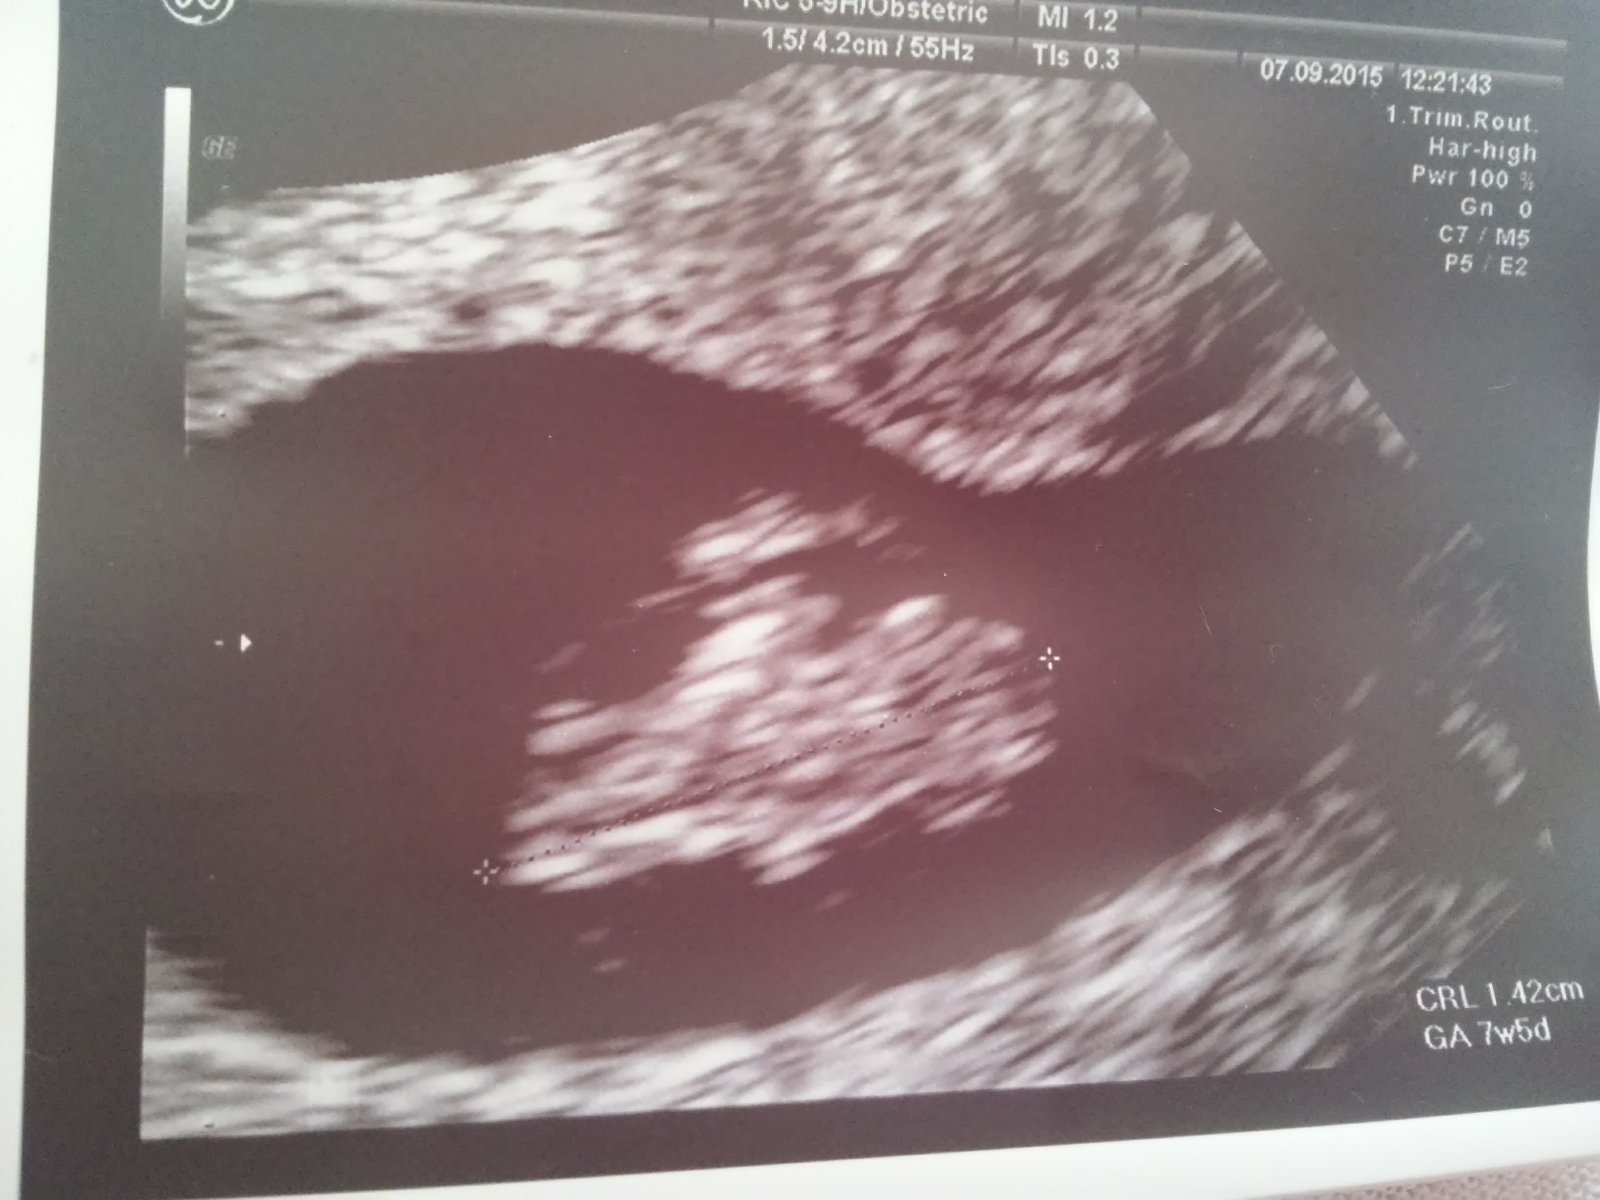

@biga7070 ahoj mam sa dobre dnes som bola na kontrolnom sone a vraj mi.porobi uz.aj odbery...tak.srdiecko.krasne bije,mame 1,42cm☺strasne sa tesim....a vraj bude usate babatko😀